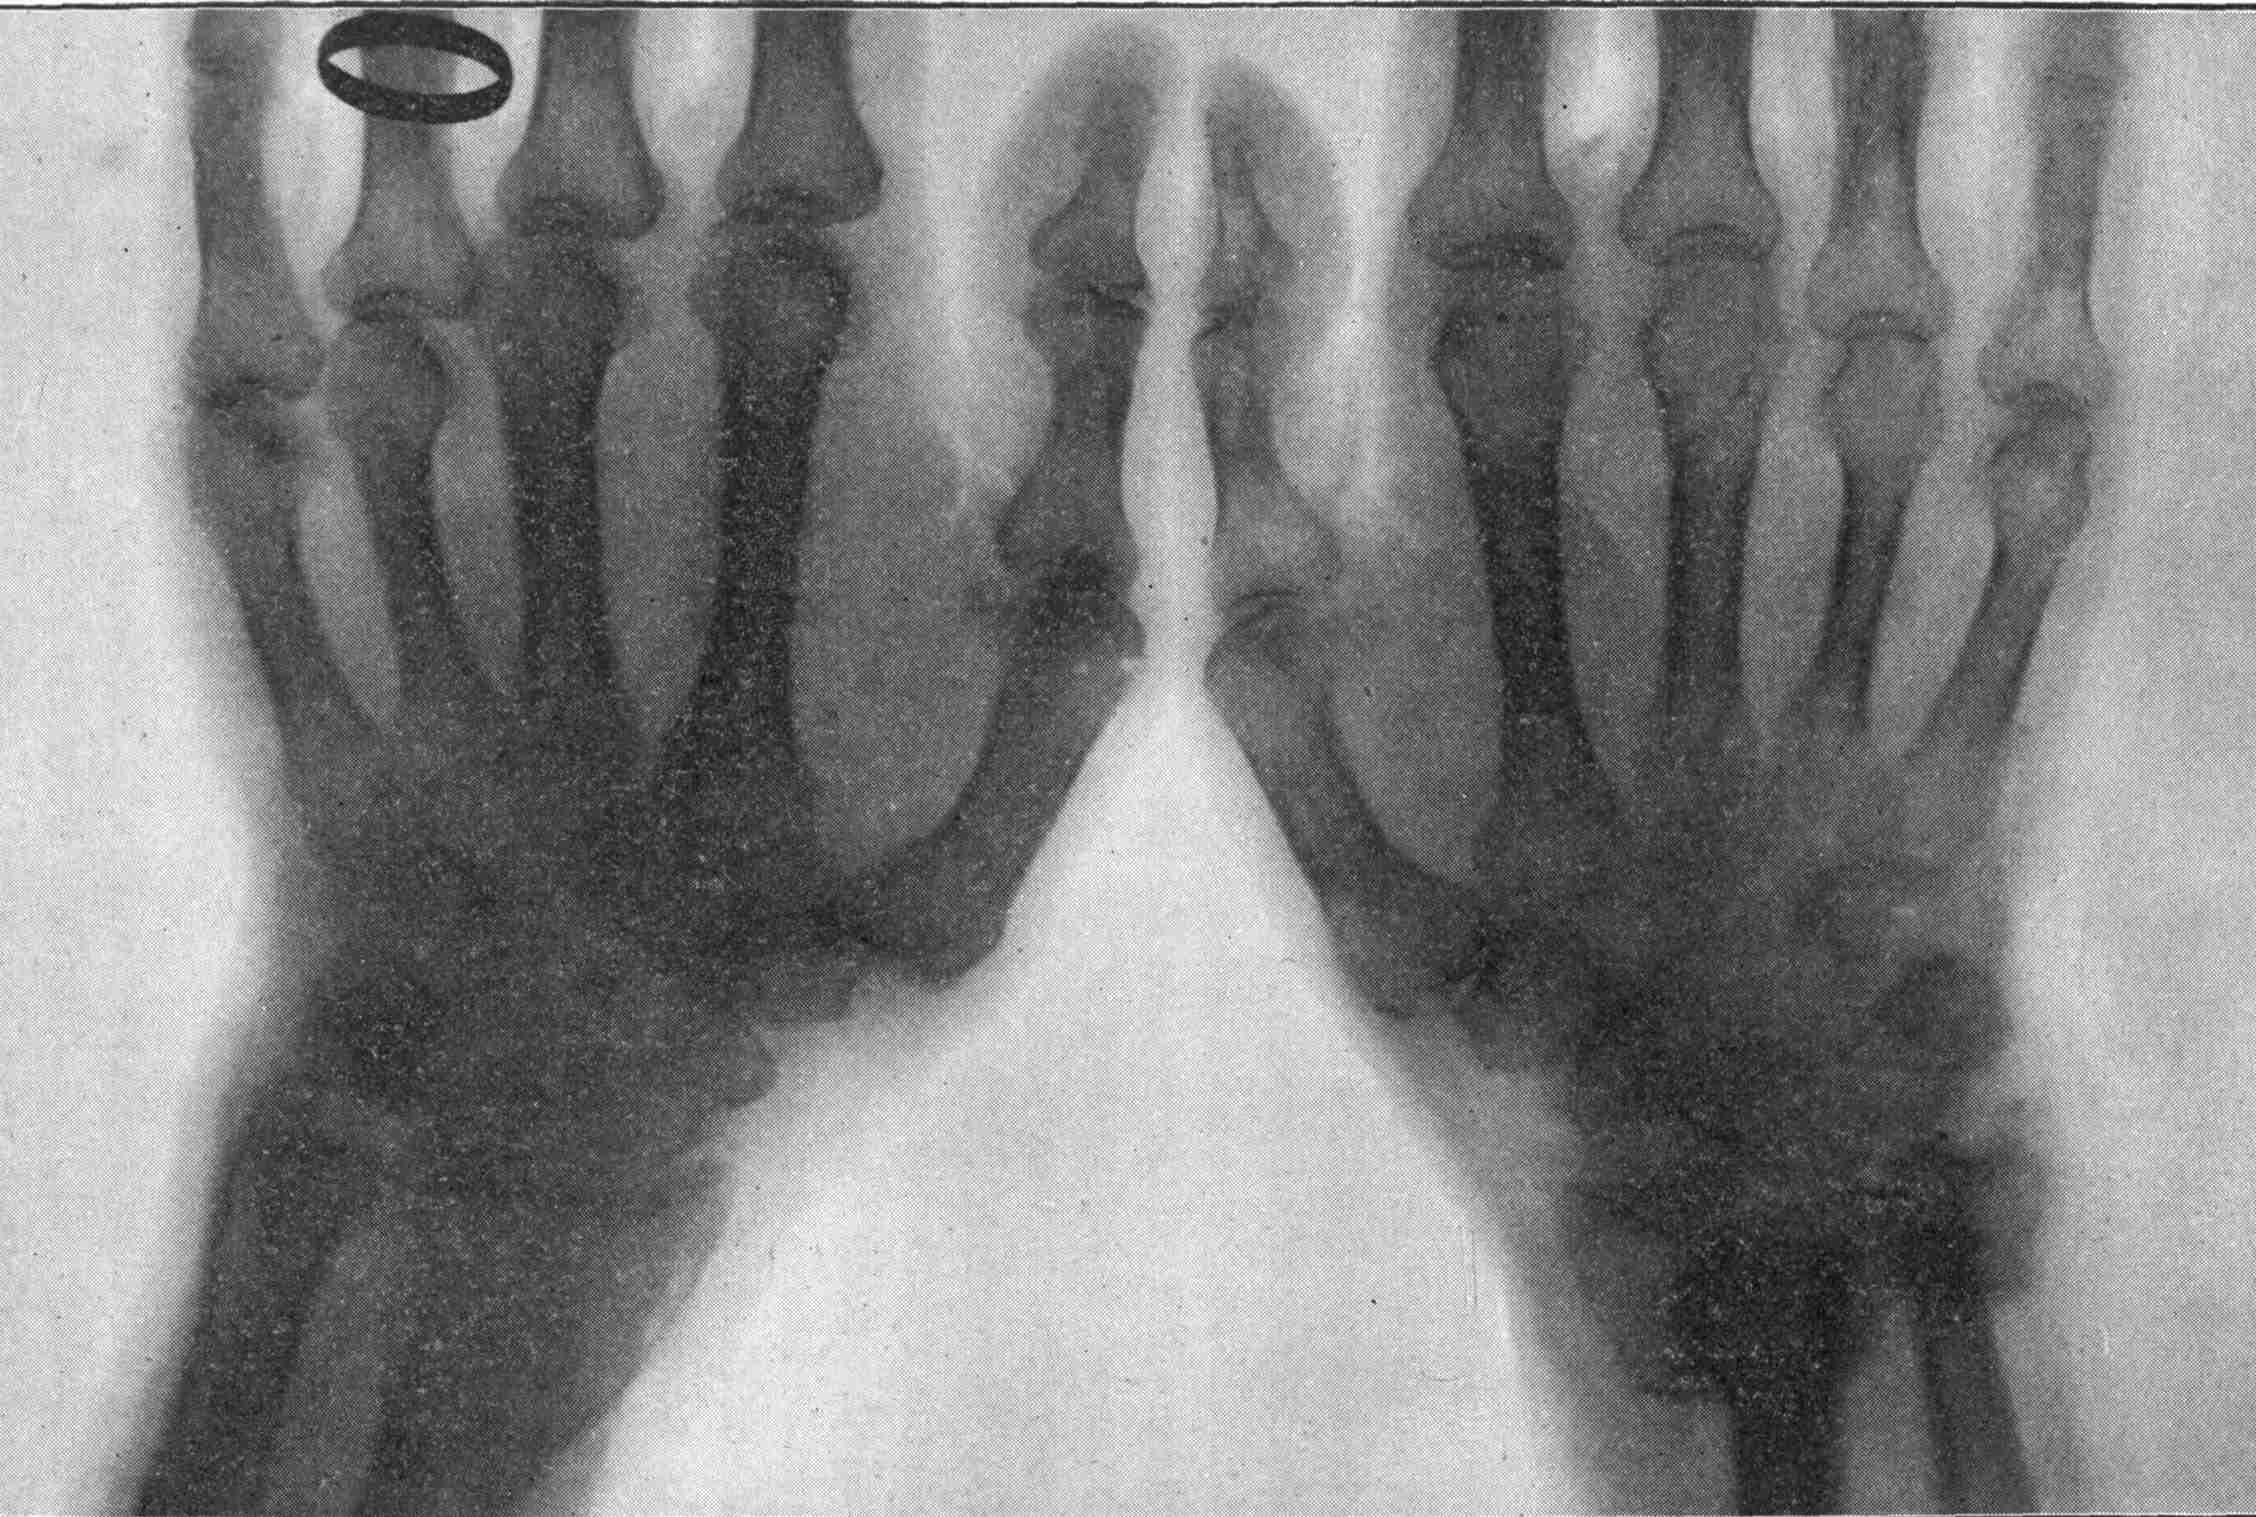

Fig. 2.—Broken Arm, Overlapping.

(Due to defective setting.)

Fig. 3.—Ribs.

Fig. 4.—Knee, Knickerbocker Buttons, Bullet in Femur.

FROM SCIAGRAPHS BY PROF. DAYTON C. MILLER. § 204.